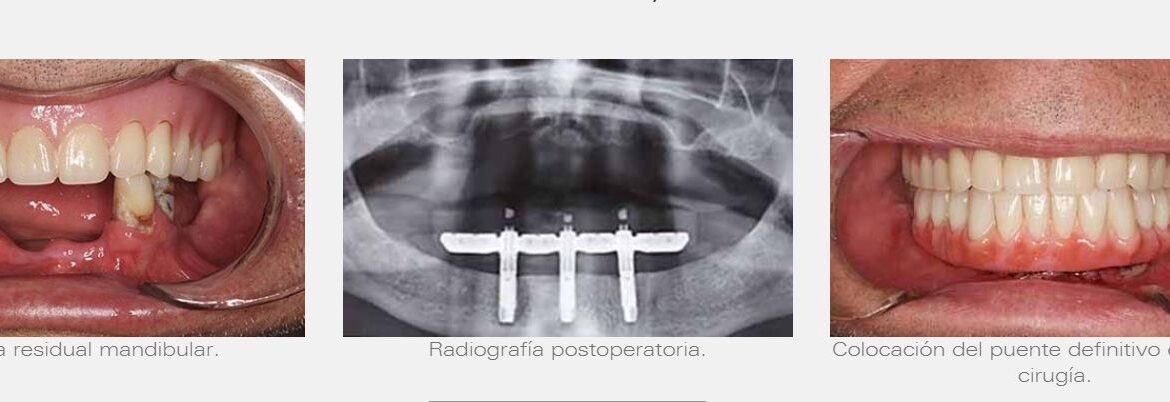

Colocación de prótesis customizada para mandíbula atrófica y lifting facial

Colocación de prótesis customizada para mandíbula atrófica y lifting facial para obtener piel y realizar la vestibuloplastia.

El diseño de la prótesis customizada comienza por un estudio de la imagen por TAC, que permite una reconstrucción en 3D de la articulación del paciente. Además el material utilizado en la intervención quirúrgica también está diseñado en base a la anatomía de la paciente.

La vestibuloplastia es un procedimiento quirúrgico, cuyo objetivo es corregir la altura de los vestíbulos bucales, es decir, el espacio que hay entre el labio y la encía, con el fin de adecuarlo, para la colocación de una prótesis, en un paciente con una mandíbula muy atrófica.